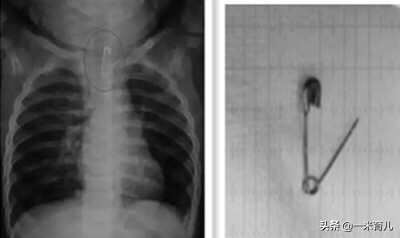

儿童吞食曲别针

儿童消化道异物大多数为:硬币、鱼刺、电池、磁性物品、玩具、毛发、别针、塑料笔帽、电动牙刷头、大头针、图钉、乳牙、笔头、枣核、鸡骨、螺丝钉等。

儿童吞食的常见物品中,硬币是最常保留在食管中的异物。